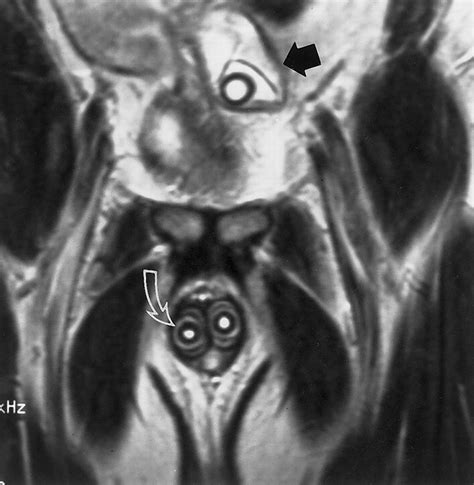

Magnetic Resonance Imaging (MRI) is a powerful diagnostic tool used in medical imaging to produce detailed images of the body's internal structures. While MRI scans are commonly associated with diagnosing various medical conditions, there are specific contexts where an MRI scan of sex-related issues can be crucial. This blog post delves into the significance, process, and implications of MRI scans in the context of sexual health and related issues.

MRI scans use strong magnetic fields and radio waves to create detailed images of the body’s internal structures. Unlike X-rays or CT scans, MRI does not use ionizing radiation, making it a safer option for repeated imaging. The technology is particularly effective in visualizing soft tissues, making it invaluable for diagnosing conditions that affect organs, muscles, and other soft tissues.

An MRI scan of sex-related issues can provide critical insights into various conditions that affect sexual health. These conditions can range from anatomical abnormalities to functional disorders. Some of the key areas where MRI scans are particularly useful include:

Interpreting MRI results involves a detailed analysis by a radiologist, who specializes in medical imaging. The radiologist will review the images to identify any abnormalities or conditions that may be affecting sexual health. Some common findings in an MRI scan of sex-related issues include: